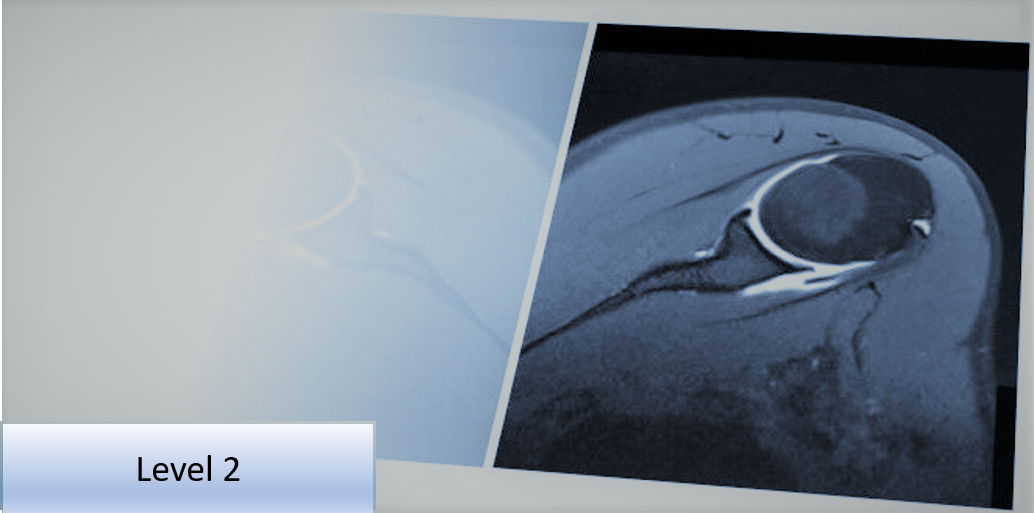

Level 2 Further Skills: Musculoskeletal Imaging Referral and Interpretation - Full Course Programme

This Level 2 course programme will provide the delegate with further skills and understanding to improve diagnostic imaging use and ensure it is clinically appropriate, thereby supporting the clinical examination.

The programme comprises three, live interactive online courses considering MSK imaging use in upper limb, lower limb and spine.

Each course uses case studies to investigate relevant common conditions and pathologies with clinical presentations and associated imaging.